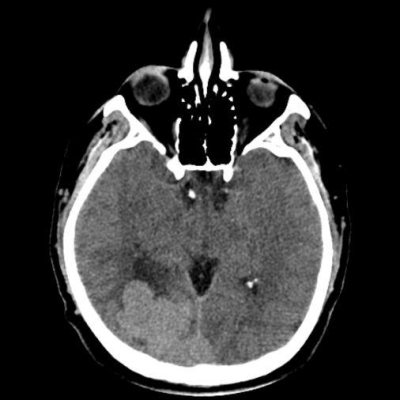

44 yaş, E

Baş ağrısı

hemorajik glioblastoma multiforme (GBM, WHO Grade 4)